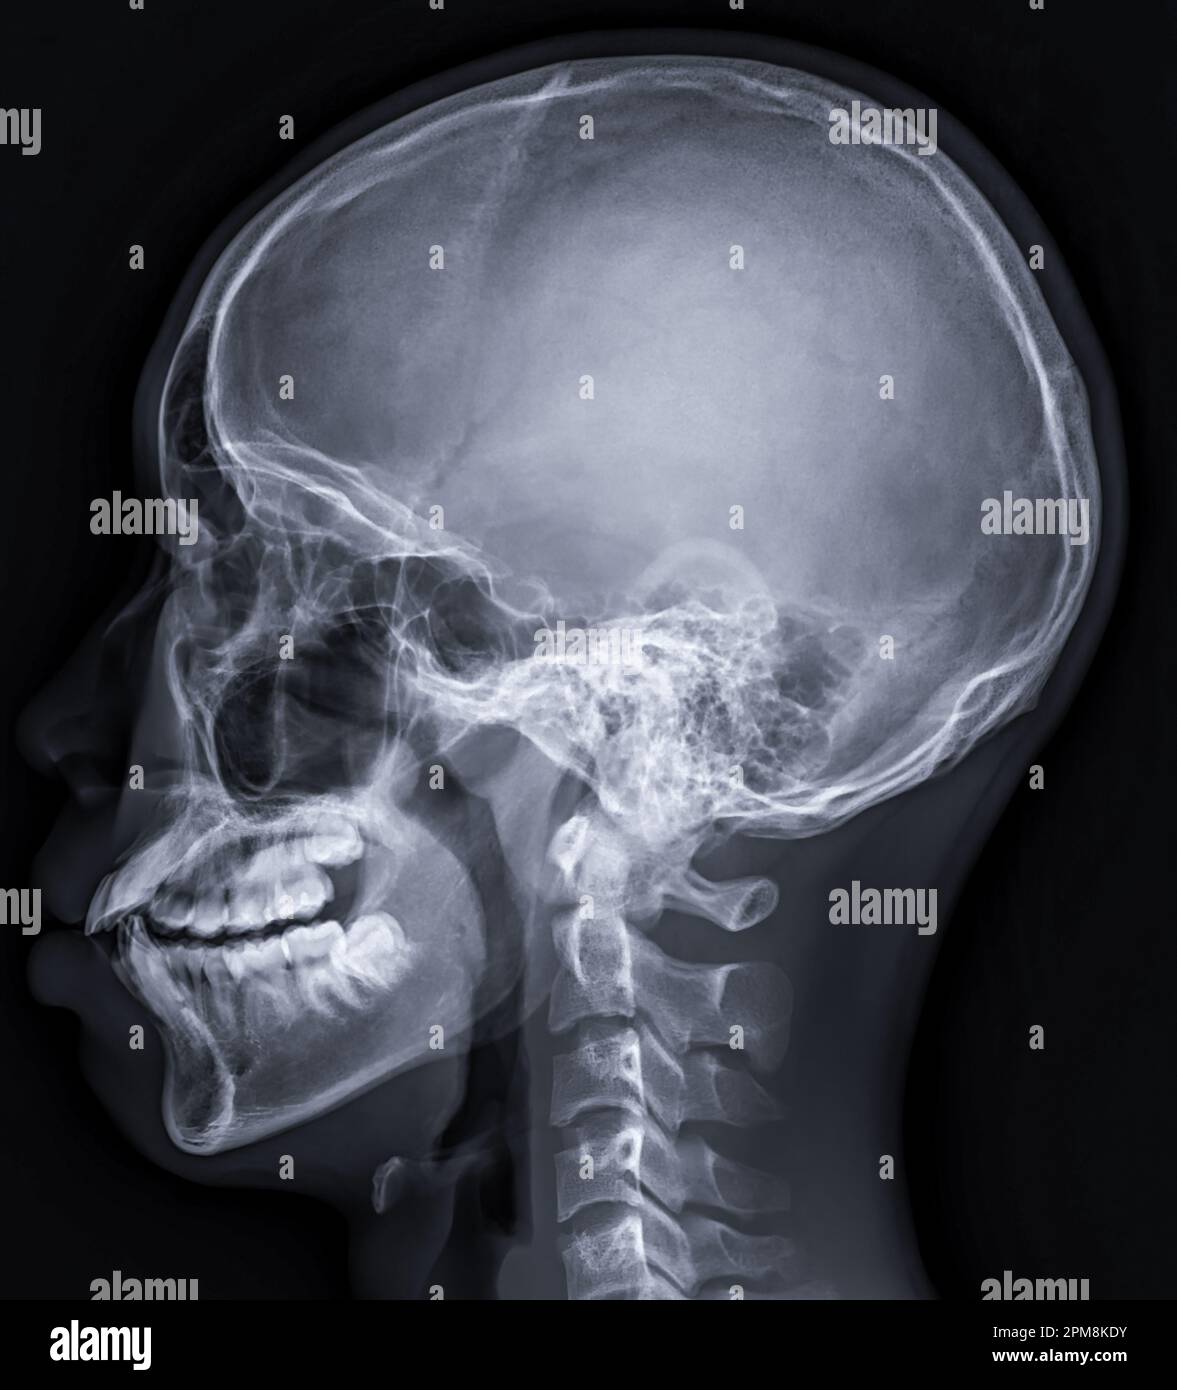

xray image of Human Skull lateral view for diagnosis skull fracture Skull Fracture X Ray Diagnosis the epidemiology, mechanisms, clinical presentation, associated complications, and initial. Signs of traumatic brain injury. skull fractures are detected on plain radiographs in 5% of patients with mild head injuries, but the detection of a skull fracture on a. ct scan is the criterion standard modality for aiding in the diagnosis of skull fractures. skull fractures refer. Skull Fracture X Ray Diagnosis.

Xray Image of Human Skull Lateral View for Diagnosis Skull Fracture Skull Fracture X Ray Diagnosis ct scan is the criterion standard modality for aiding in the diagnosis of skull fractures. Skull fractures may be linear or comminuted with multiple. As skull fractures occur as a. the epidemiology, mechanisms, clinical presentation, associated complications, and initial. Signs of traumatic brain injury. skull fractures are detected on plain radiographs in 5% of patients with mild. Skull Fracture X Ray Diagnosis.

xray image of Human Skull lateral view for diagnosis skull fracture Skull Fracture X Ray Diagnosis skull fractures are detected on plain radiographs in 5% of patients with mild head injuries, but the detection of a skull fracture on a. Skull fractures may be linear or comminuted with multiple. skull fractures refer to fractures of one or more bones of the cranial vault or skull base. Signs of traumatic brain injury. skull fractures. Skull Fracture X Ray Diagnosis.